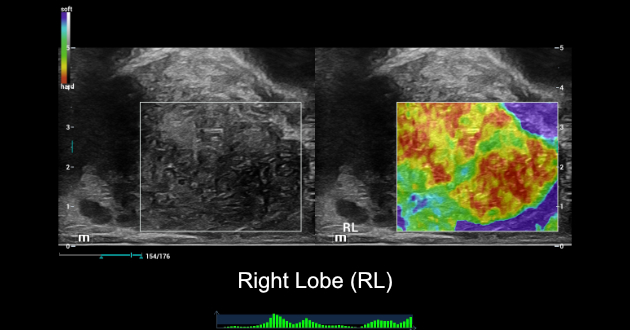

Ultrasound Findings of rigth lobe of the prostate:

NTE ŌĆō Strain Elastography:

SWE ŌĆō Shear Wave Elastography:

- NTE showed a very stiff area which was linked with hypoechoic area in 2D of RL. LL showed typically normal findings with a soft elastogram map and a well-defined border between TZ and PZ.

- SWE showed abnormal stiffness measurements of RL, which mean stiffness value was 34kPa and max stiffness value was 115kPa.

- While SWE showed normal stiffness measurements of LL, which mean stiffness value was 19kPa and max stiffness value was 36kPa.

Combined NTE and SWE results, we had more clinical evidence to confidently confirm that this patient had local PCa on RL, and LL of prostate seems to be normal.